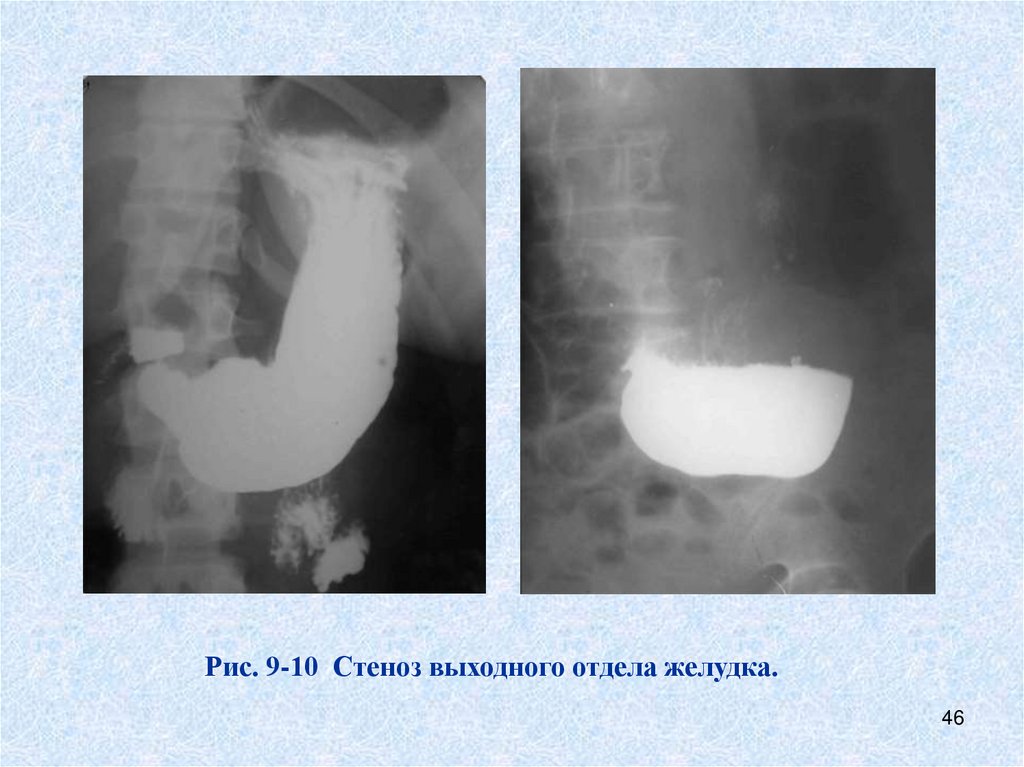

Рис. 9-10 Стеноз выходного отдела желудка.